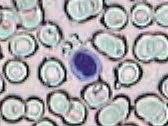

Imágenes tomadas de las preparaciones de los alumnos de 3º ESO sobre un frotis sanguíneo

168x126 píxeles